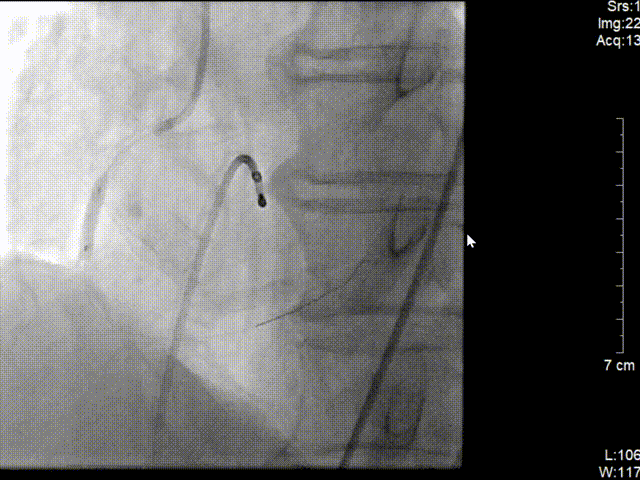

冠脉造影结果(右冠近段病变)

冠脉三支病变 右冠近端完全闭塞病变。

左图:6F JR4.0指引导管造影。

在J型导丝指引下6F JR4.0指引导管于右冠口,行造影提示右冠近段急性闭塞,将SION blue导丝操作通过右冠近端闭塞处并达远段真腔,予2.0*15预扩张球囊行病变处预扩张处理,复查造影可见血栓,予血栓抽吸导管反复抽吸,抽出大量红色血栓。